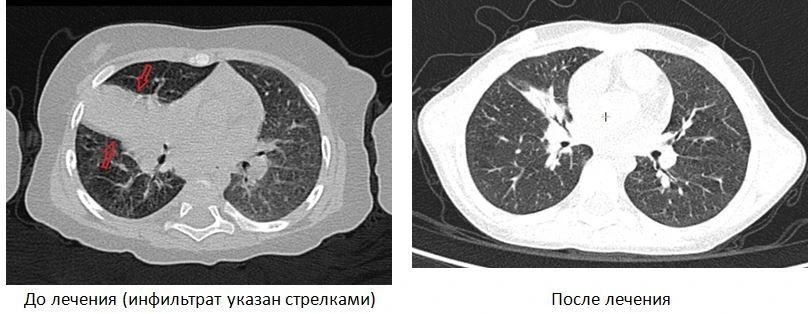

Врачи провели сложное диагностическое исследование бронхов под наркозом, а также компьютерную томографию легких. Был установлен диагноз осложненного туберкулеза. Специалисты подобрали индивидуальную схему лечения, которая продолжалась более года. За это время девочке неоднократно проводили лечебные процедуры и контрольные обследования.

Благодаря профессионализму детских фтизиатров больницы, ребенок пошел на поправку и полностью выздоровел. Сейчас девочка растет и развивается как все здоровые дети.